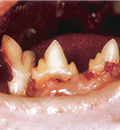

10-2. 고양이 치아 흡수성 병변 (FORL, feline odontoclastic resorptive lesion)

- 고양이 치아 흡수성 병변은 가장 많이 진단되는 고양이 치과질환 중 하나입니다.

이 질환은 파치아세포가 출현하여 나타나는 병변으로 통상 치아의 뺨쪽면의 잇몸변연 바로 아래쪽에 주로 발생합니다. 하지만 모든 치아의 크라운이나 뿌리 어느 면에서도 발생할 수 있습니다.

정확한 발병원인은 아직 밝혀지지 않았습니다. 발치가 가장 추천되는 방법이며 평소 정기적인 구강위생(칫솔질과 주기적인 스케일링)도 권장됩니다.